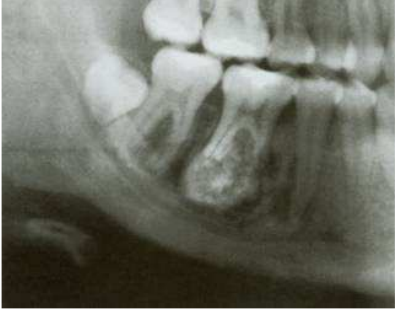

76.一位25歲男性患者數年前感覺右下顎第一大臼齒處疼痛,當時牙醫師從根尖片看到放射線透性病灶圍繞第一大臼齒根尖部位,該牙牙髓活性測試為活性 反應,因而建議患者定期追蹤檢查。失聯了一陣子,患者又來看診,從顎全景攝影X光片(如下圖)發現該牙根部貼附一放射線不透性病灶、周圍有一圈 放射線透性區域,牙根有外吸收現象,但牙髓仍呈活性反應。在鑑別診斷時,下列何者較不可能?

(A)根尖牙骨質發育不良(periapical cemental dysplasia) (B)良性牙骨質母細胞瘤(benign cementoblastoma) (C)成骨細胞瘤(osteoblastoma) (D)纖維性發育不良(fibrous dysplasia)